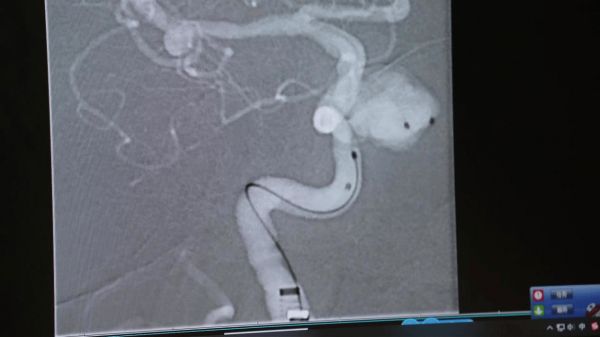

若需干预,现代医学已基本告别传统开颅手术的有创模式。自2002年起,国际多中心研究已确立微创介入治疗作为颅内动脉瘤的首选方案。这一技术迭代,正是国家鼓励临床创新、推进高端医疗器械自主研发的生动实践,让“大病不出省、小病不出县”的愿景在脑血管病领域逐步落地。